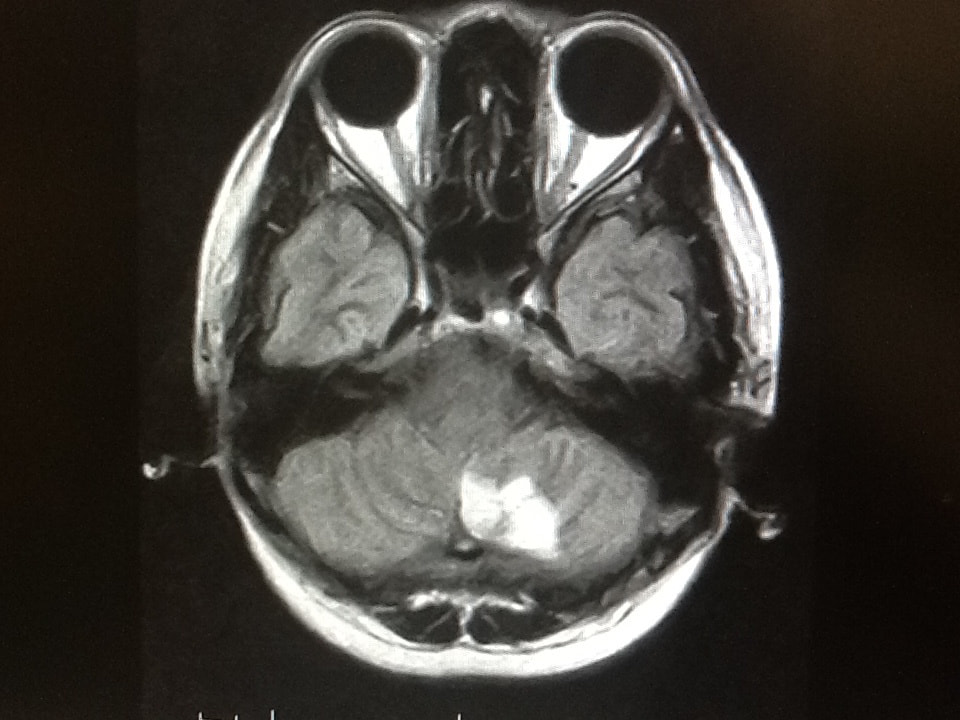

病気の早期発見のために、最新のMRIを用いた本格的な検診。

大病院などで用いられている最新のMRIを使用し、精度の高い結果を得、かつ痛みや不快感を極力排除することを可能にしました。